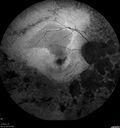

82 year old man with a sister with RP and no other family members. He has trouble with night vision. VA 20/25 OD, 20/32 OS. Note the symmetry in the FAF images typical for a dystrophy. The photos show bone spicules, arteriol attenuation and optic nerve pallor

Retinitis Pigmentosa - Autosomal Recessive - 82 year old man with Good Vision481 viewsVA 20/25, 20/32 - Bone spicules in periphery - FAF is very symmetric     (0 votes)